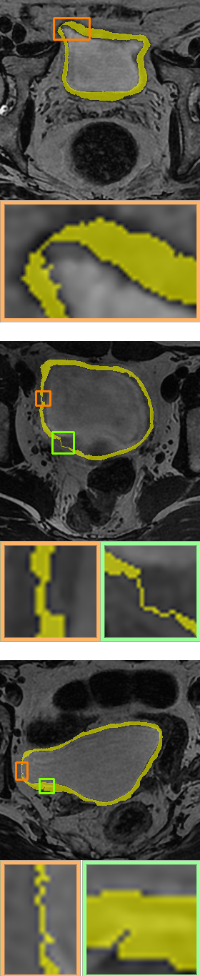

In this section, we will add two different topological energies to Topo-NLSTD model Eq. 13. For convenience, when adding energy without width information Eq. 11, it is denoted as PH; when adding width-aware topological energy Eq. 12, it is denoted as WT. Fig. 7, Fig. 8 and Fig. 9 show the results on synthetic images, the International Symposium on Image Computing and Digital Medicine (ISICDM) 2019 dataset [isicdm] and the Massachusetts Roads dataset [mass], respectively. From the results, we can see that NLSTD retains more image information compared to STD rather than performing a simple smoothing. Then, the results of PH are usually connected to a single-pixel width line or a single-pixel genus to satisfy a given topological constraint. In contrast, our proposed energy not only maintains the topological consistency well, but also fuses the width information.

Image

UNet[unet]

STD[std]

NLSTD[densecrf]

PH[ph]

Proposed WT